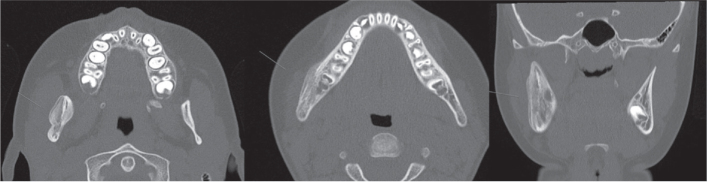

Abstract Image